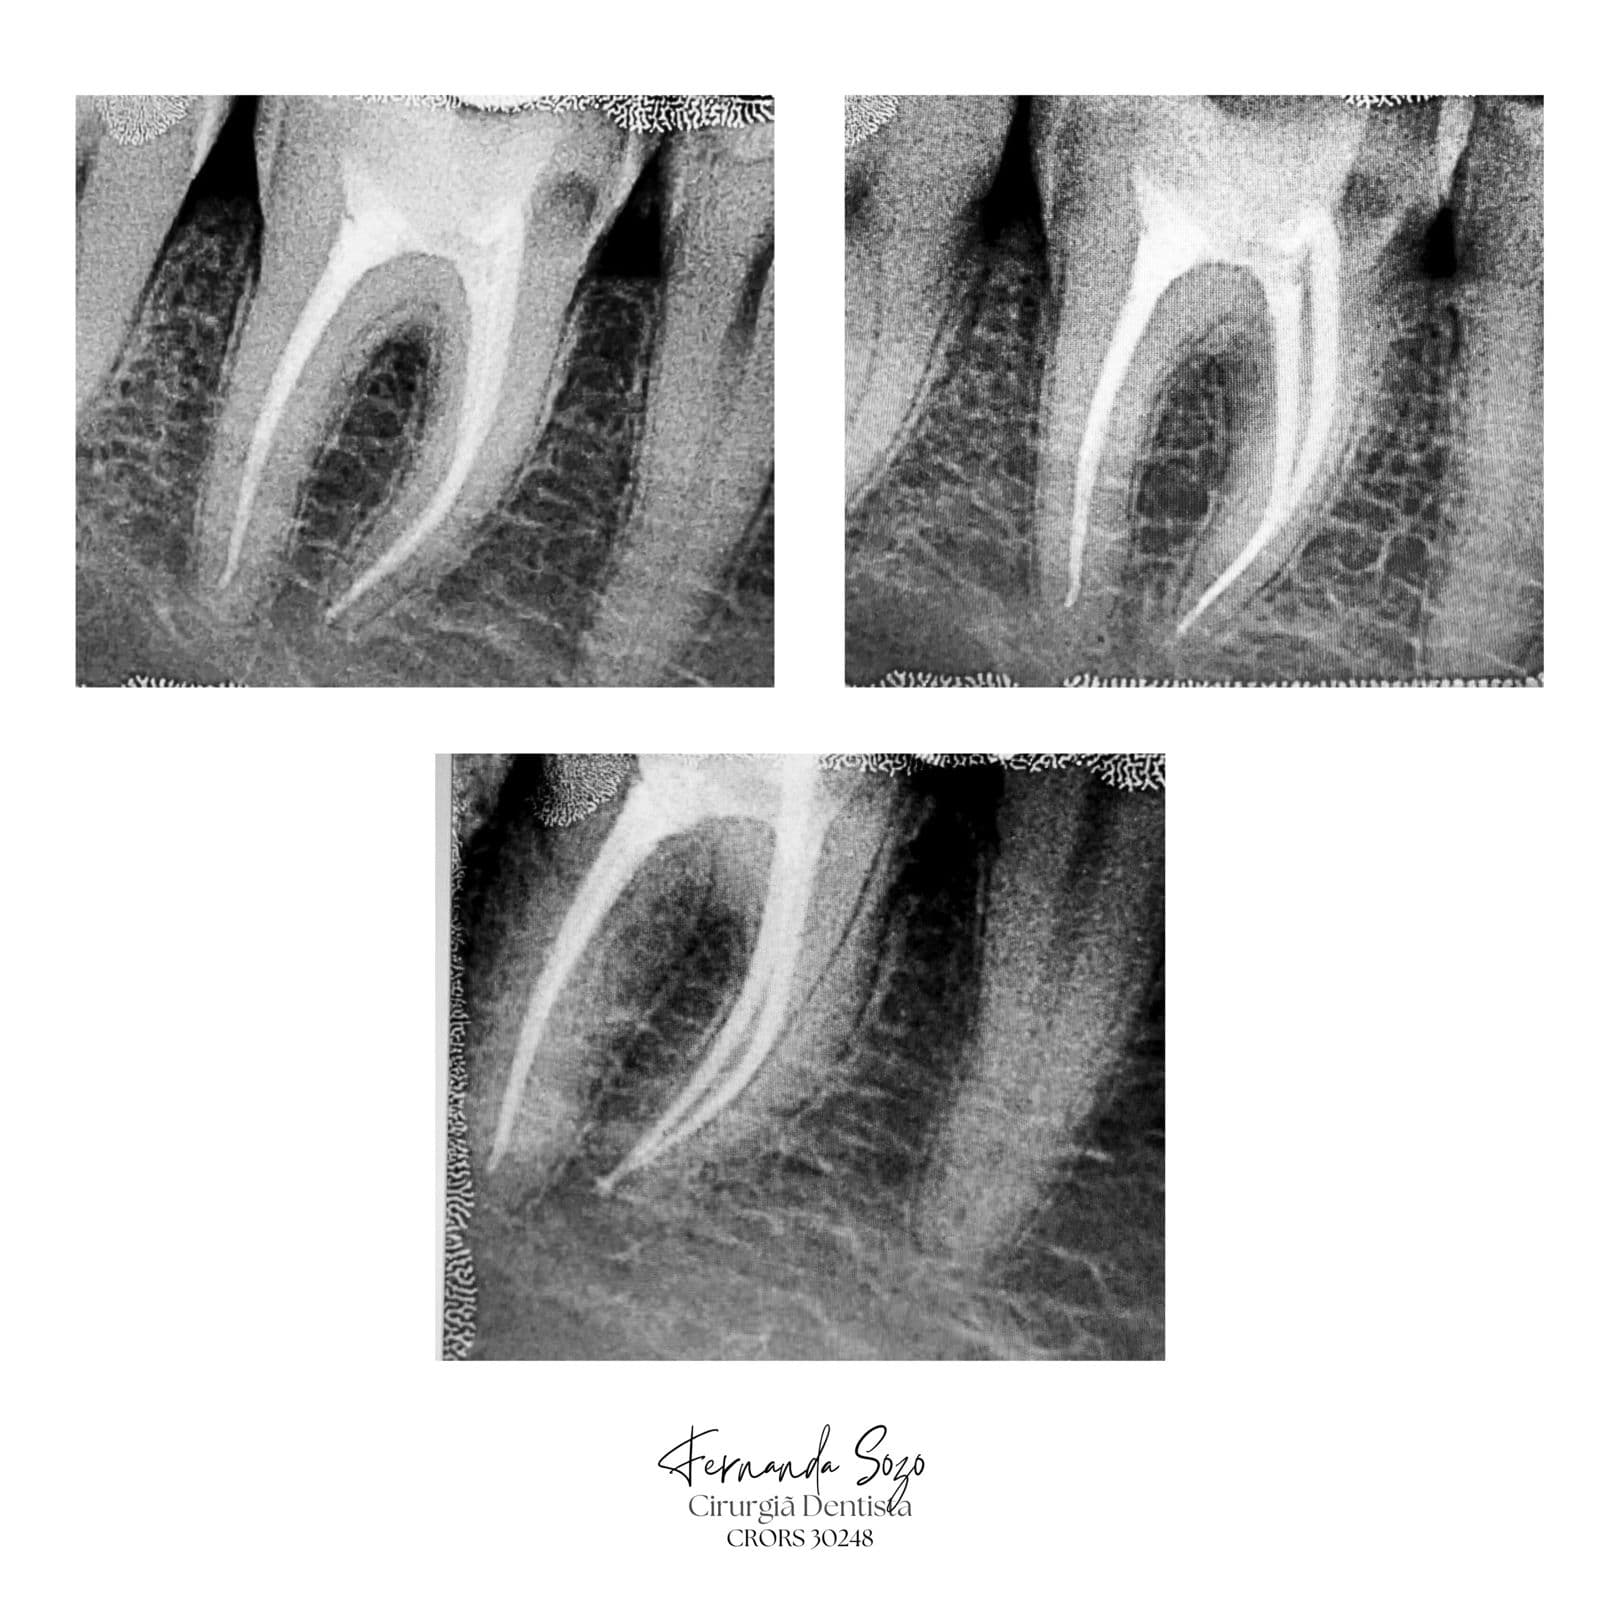

Portfólio

Casos Clínicos

Resultados que demonstram precisão técnica e excelência.